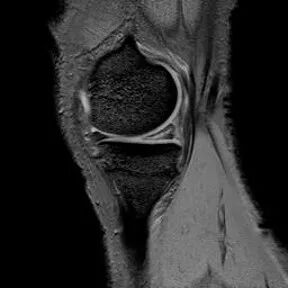

半月板桶柄状撕裂

1、多为纵形撕裂的特殊形式,有时来源于垂直(纵行)和水平撕裂2、多见于严重外伤的年轻患者3、内侧半月板发生率是外侧半月板的3倍

桶柄状撕裂MRI表现

1、宽度减小,在通过半月板体部的冠状面上蝶形消失,同时可见内移的半月板位于髁间窝、交叉韧带旁2、矢状面示残余的前角或后角变小或截断3、半月板前(后)角增宽或双半月板前(后)角征4、双前交叉韧带或双后交叉韧带征

桶柄状撕裂:宽度减小,在通过半月板体部的冠状面上蝶形消失,同时可见内移的半月板位于髁间窝、交叉韧带旁

桶柄状撕裂:半月板后角增宽